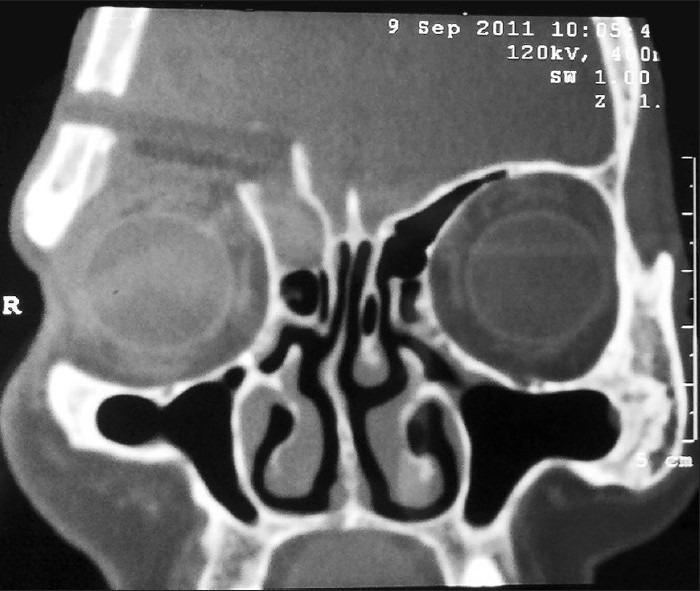

A mucocele of a para-nasal sinus is an accumulation of mucoid secretion and desqua-mated epithelium within the sinus with distension of its walls and is regarded as a cyst like expansile and destructive lesion. If the cyst invades the adjacent orbit and continues to expand within the orbital cavity, the mass may mimic the behavior of many benign growths primary in the orbit. The frontal sinus is most commonly involved, whereas sphenoid, ethmoid, and maxillary mucoceles are rare. Floor of frontal sinus is shared with the superior orbital wall which explains the early displacement of orbit in enlarging frontal mucoceles. Frontal sinus mucoceles are prone to recurrences if not managed adequately. Here, we are evaluating different approaches used to manage various stages of frontal mucoceles which presented to us with orbital complications. Three cases of frontal sinus mucocele are discussed which presented to our OPD with different clinical symptoms and all cases were managed by different surgical approaches according to their severity. We also concluded that it is prudent to collaborate with the neurosurgeons for adequate management of such complex mucoceles by a craniotomy approach.

鼻窦黏液囊肿是鼻窦内黏液样分泌物和脱落上皮的积聚,伴有鼻窦壁扩张,被视为一种类似囊肿的膨胀性破坏性病变。如果囊肿侵犯相邻眼眶并在眶腔内持续扩大,肿块可能类似许多眼眶原发性良性肿瘤的表现。额窦最常受累,而蝶窦、筛窦和上颌窦黏液囊肿罕见。额窦底部与眶上壁相邻,这解释了额窦黏液囊肿增大时眼眶早期移位的原因。如果处理不当,额窦黏液囊肿容易复发。在此,我们评估了用于处理出现眼眶并发症的不同阶段额窦黏液囊肿的不同方法。讨论了3例因不同临床症状就诊于我们门诊的额窦黏液囊肿病例,所有病例均根据其严重程度采用不同的手术方法进行处理。我们还得出结论,对于此类复杂黏液囊肿,通过开颅手术方法进行充分处理时,与神经外科医生合作是明智的。